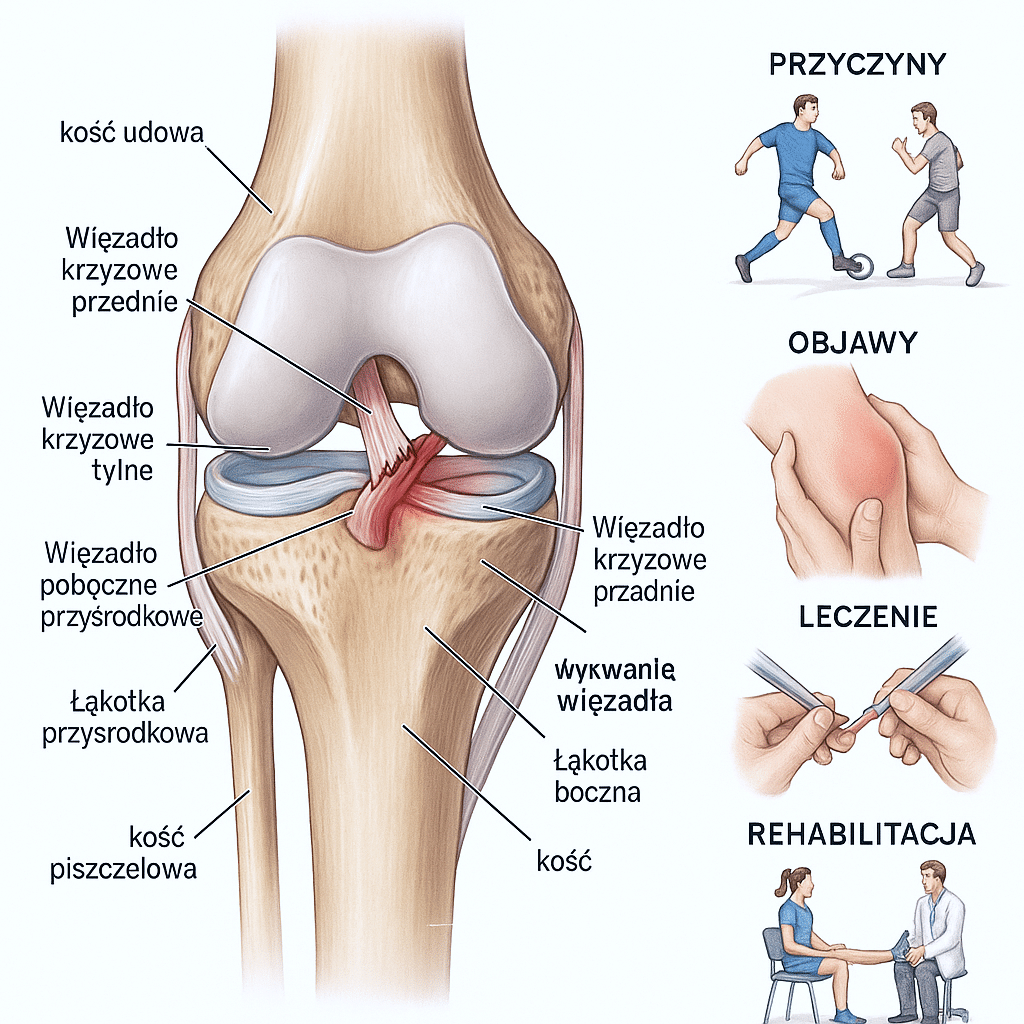

W obrębie kolana wyróżniamy kilka głównych więzadeł:

- więzadło krzyżowe przednie (ACL),

- więzadło krzyżowe tylne (PCL),

- więzadło poboczne przyśrodkowe (MCL),

- więzadło poboczne boczne (LCL),

- więzadło rzepki.

Każde z nich pełni odrębną, ale równie istotną rolę. ACL zapobiega nadmiernemu przesuwaniu się kości piszczelowej względem kości udowej do przodu oraz ogranicza ruchy rotacyjne, co jest szczególnie ważne podczas gwałtownych zmian kierunku ruchu. PCL chroni przed przemieszczaniem się piszczeli do tyłu, natomiast więzadła poboczne stabilizują kolano w płaszczyźnie bocznej i przyśrodkowej, zabezpieczając je przed niekontrolowanymi wychyleniami na boki.

- Zerwanie więzadła najczęściej wynika z nagłych skrętów, gwałtownych zatrzymań, bezpośrednich uderzeń lub przeciążeń. Szczególnie narażone są osoby uprawiające sporty dynamiczne, ale uraz może dotyczyć każdego, także podczas zwykłych upadków czy potknięć.

- Charakterystyczne objawy zerwania więzadła to: silny ból, szybki obrzęk, uczucie niestabilności kolana oraz ograniczenie zakresu ruchu.

- Leczenie zerwanych więzadeł obejmuje zarówno metody zachowawcze (odpoczynek, unieruchomienie, rehabilitacja), jak i operacyjne (rekonstrukcja więzadła). Czas powrotu do pełnej sprawności zależy od stopnia urazu i zaangażowania w rehabilitację (od kilku tygodni przy naciągnięciu do nawet roku po operacji).